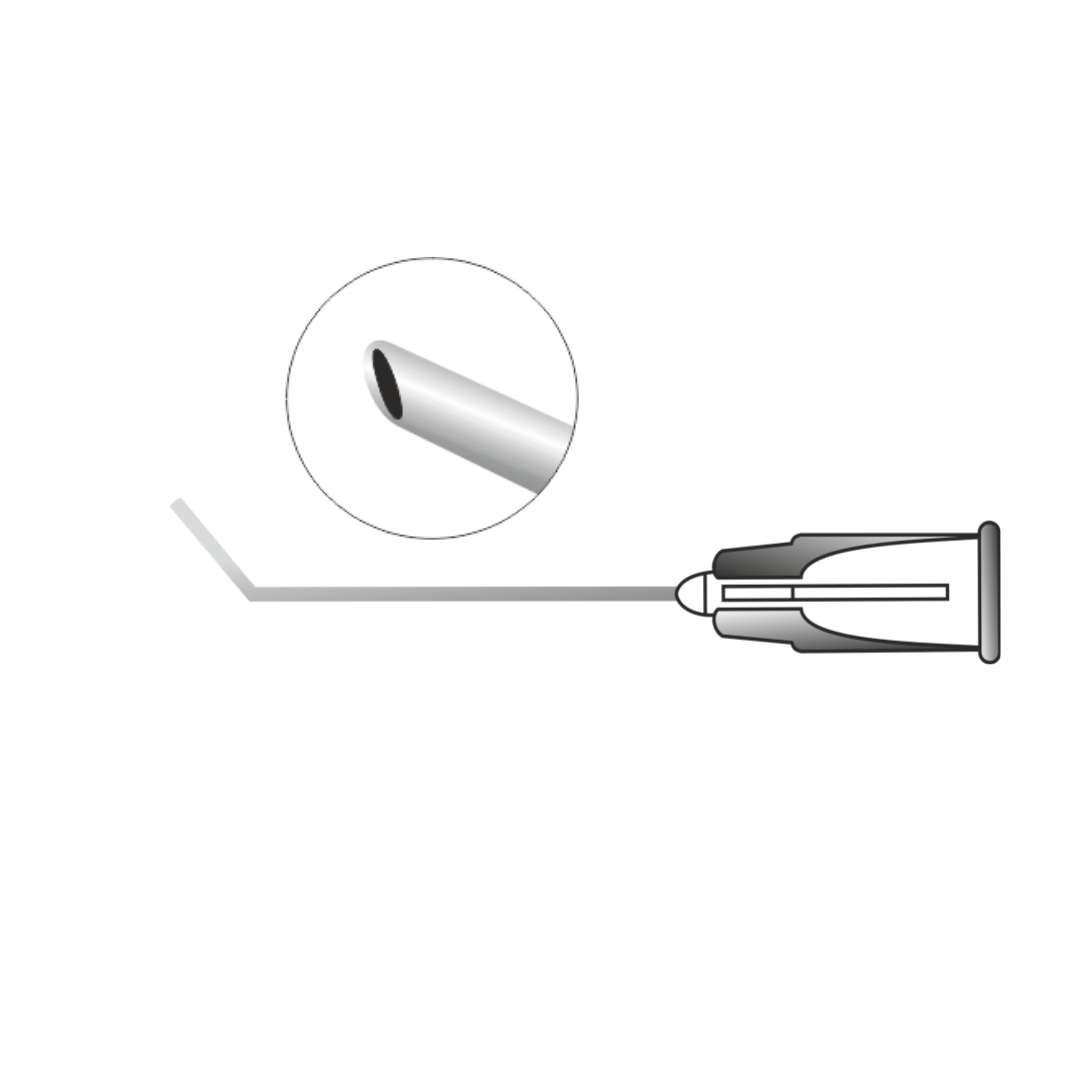

Description

A precision ophthalmic cannula designed for controlled fluid injection during cataract surgery to separate the lens nucleus from the capsule. It facilitates smooth nucleus rotation and safe cortical removal by creating a balanced fluid wave. Manufactured with a fine, atraumatic tip to ensure accurate hydro dissection and enhanced surgical control.

Available in disposable and Reusable